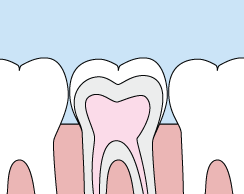

Crowns are most often used for teeth that are broken, worn, or have portions destroyed by tooth decay. They restore a broken down tooth to it's original form and function and can protect a cracked tooth from breaking. Crowns can also be used as a cosmetic treatment to change the color or alignment of one, two or several teeth.

A crown is a "cap" cemented onto an existing tooth that usually covers the portion of your tooth above the gum line. In effect, the crown becomes your tooth’s new outer surface. Crowns can be made of porcelain, metal, or both. Porcelain crowns are most often preferred because they mimic the translucency of natural teeth and are very strong.

Crowns or onlays (partial crowns) are needed when there is insufficient tooth strength remaining to hold a filling. Unlike fillings, which apply the restorative material directly into your mouth, a crown is fabricated away from your mouth. Your crown is created in a lab from your unique tooth impression, which allows our dental laboratory technician to examine all aspects of your bite and jaw movements. Your crown is then sculpted just for you so that your bite and jaw movements function normally once the crown is placed.